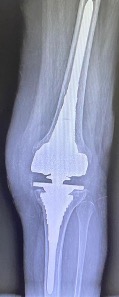

Revision total knee arthroplasty (rTKA) poses significant challenges in achieving stable, long-term fixation, particularly when residual bone stock is compromised1. The integrity of the metaphyseal region is crucial for attaining optimal stability in a revision construct. This area, due to its rich vascularization and reduced susceptibility to surgical damage compared to the epiphyseal bone, facilitates cement interdigitation and implant osteointegration, contributing to superior initial fixation and prolonged implant survival2. In cases with substantial bone defects, two commonly adopted global approaches leverage these properties: the use of cones and metaphyseal sleeves3. These constructs differ significantly. Cones, which serve as fillers, are used to fill defect sizes and enhance the fixation of cemented implants without structural integration with other components. In contrast, metaphyseal sleeves are integrated parts of the implant, providing primary and direct fixation while aiding in load transfer from the revision components to the metaphyseal region. Additionally, metaphyseal sleeves offer the potential for bony biologic fixation, improving rotational stability and protecting epiphyseal fixation. Compared to fluted cylindrical stems, metaphyseal sleeves are more effective in achieving these objectives4. Clinicians typically use stems initially to stabilize sleeves (Figure 1), but there is an increasing trend toward using sleeves without stems (Figure 2). However, studies on this approach are limited by small sample sizes, lack of control groups, and short follow-up periods. Importantly, there is currently no consensus on the necessity of using stems with metaphyseal sleeves. This systematic review aims to summarize the contemporary literature to determine whether using metaphyseal sleeves without stems in rTKA is a valuable option.

Figure 1. Stemmed sleeve configuration in revision total knee arthroplasty.